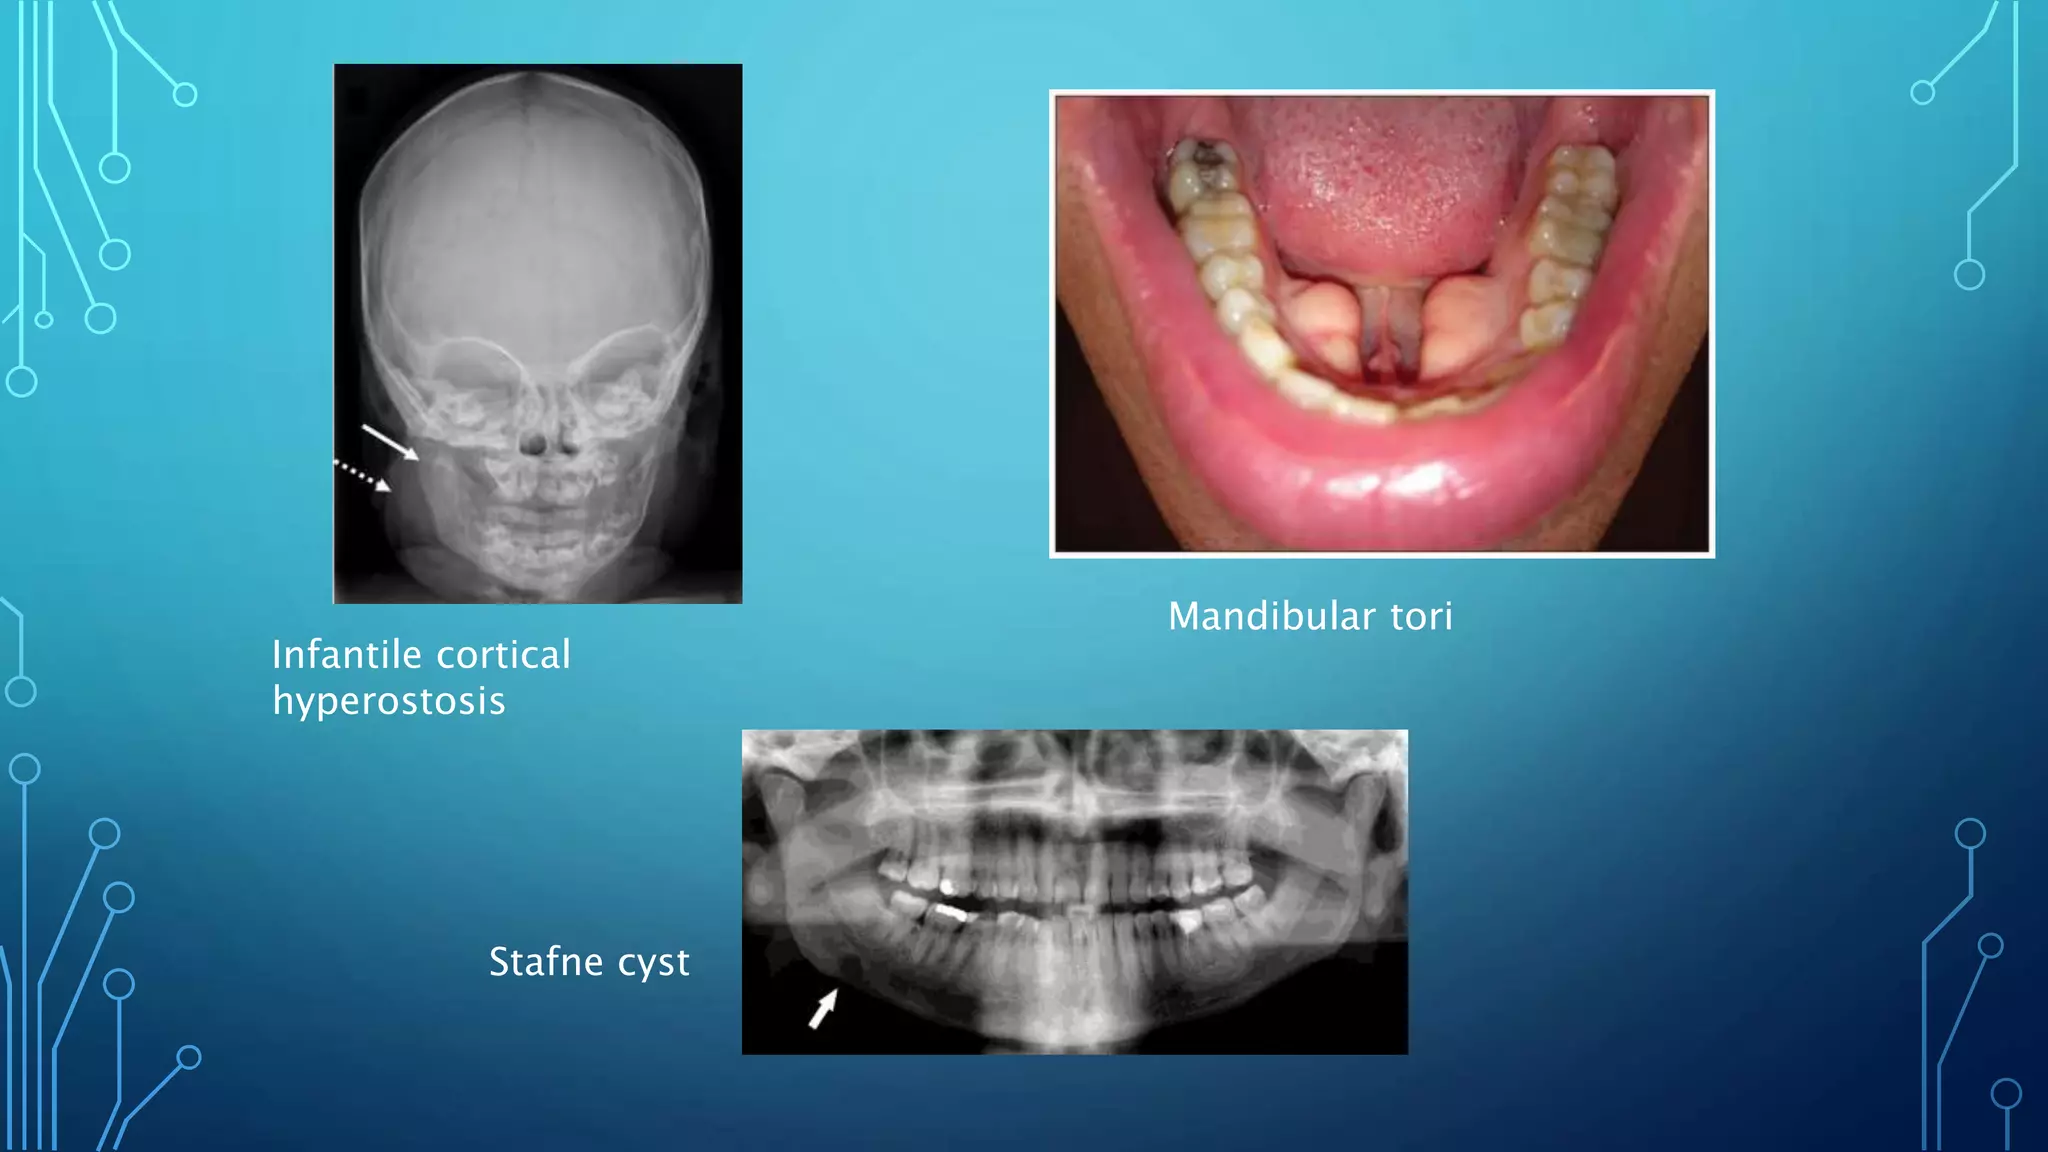

DEVELOPMENTAL

• Infantile cortical

hyperostosis

• Achondroplasia

• Torus mandibularis

• Stafne’s cyst

Infantile cortical

Stafne cyst

Mandibular tori